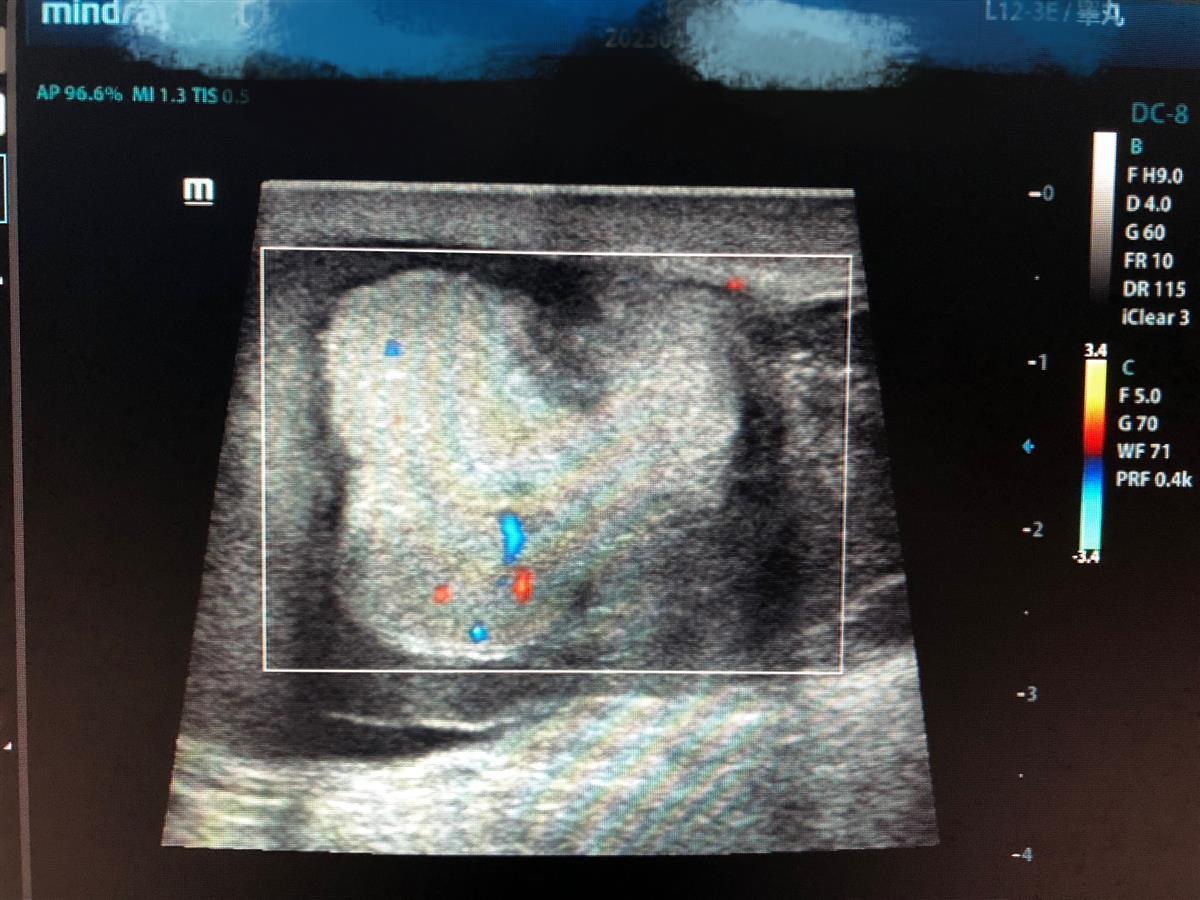

“医生,快帮我儿子看看,他上午和同学一起踢足球,不小心被球踢到了下体,一直喊疼,这会还有点肿。”6月28日中午,17岁男孩在父亲的陪同下走进武汉市第四医院泌尿外科诊室,焦急地向医生介绍了事发情况。初步检查后,超声科医生雷琳为其检查。通过影像结果,医生发现男孩左侧睾丸已失去正常形态,血供明显减少,周边都是积血包绕,基本可以判断左侧睾丸破裂、出血,急需手术。

男孩的影像检查结果